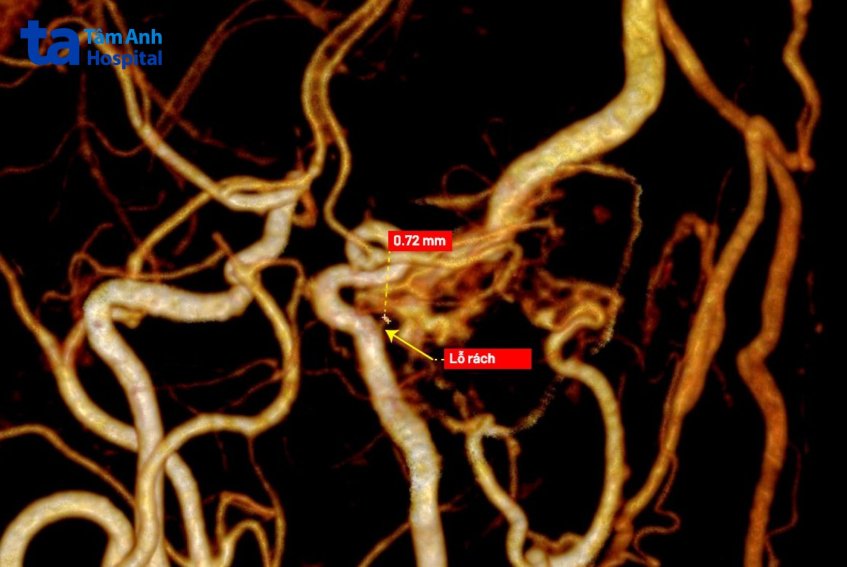

Ekip can thiệp đặt coils (vòng xoắn) để bít tắc điểm rò, tái lập dòng chảy bình thường trong động mạch cho người bệnh. Nhờ chụp bằng máy CT Somatom Force VB30 có độ dày lát cắt chỉ 0,4 mm, bác sĩ tìm được điểm rò đường kính chỉ khoảng 0,7 mm – rất khó thấy nếu chụp bằng máy CT thông thường. Máy còn giúp dựng hình 3D, 4D toàn bộ mạch máu, hỗ trợ bác sĩ thăm dò chính xác điểm rò và hướng rò để có kế hoạch can thiệp phù hợp.